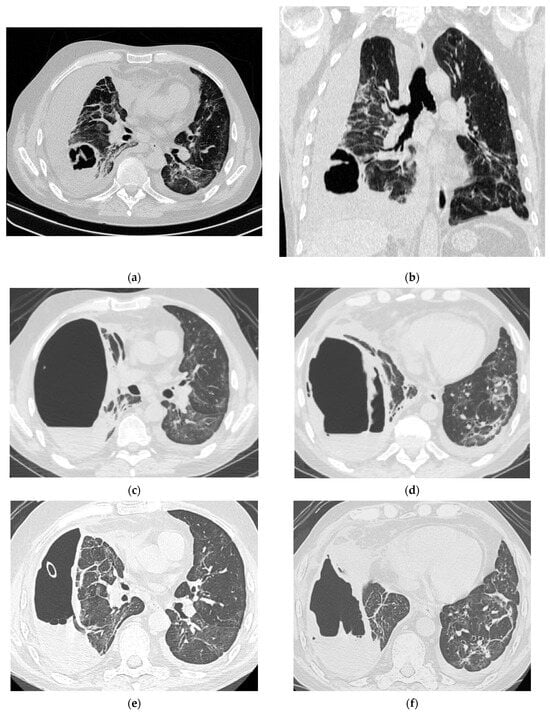

Figure 3.

Radiologic evolution of case 1: Initial chest CT scan (axial and coronal plane) showing right lower lobe abscess prior to rupture into pleural space and post-COVID-19 infection infiltrates (a,b). CT scan after abscess rupture and prior to percutaneous drainage showing air cavity with dense fluid and hydro-aeric level occupying almost the entire right lung field; remaining right lung parenchyma with fibrotic changes, and a large lung abscess compressed at the hilum; small left pleural collection; small pericardial effusion (c,d). After the insertion of percutaneous ICD, CT scans follow-up reveals decreased volume of the residual cavity, thickened pleura and intracavitary drainage (e); slightly re-expanded right lung parenchyma; numerous ground-glass opacities (GGO), areas of fibrosis and passive atelectasis (e,f). After chest tube removal (290 days of drainage), minimal residual cavity without fluid and thin pleural fibrotic changes remained (g,h).